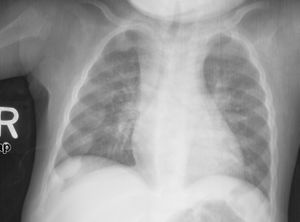

An X-ray or radiograph of an advanced sufferer from rickets tends to present in a classic way: bow legs (outward curve of long bone of the legs) and a deformed chest. Changes in the skull also occur causing a distinctive "square headed" appearance (Caput Quadratum). These deformities persist into adult life if not treated. Long-term consequences include permanent bends or disfiguration of the long bones, and a curved back.[5]

تجس عقيدات كحبات السبحة ناجمة عن تضخم الغضاريف في مناطق الوصل القصي الضلعي، وقد تكون مرئية للعين أيضاً. يتبارز القص إلى الأمام ويسبب تشوهاً (صدر الحمامة) كما يحدث انخفاض للداخل على طول الحافة السفلية للأضلاع يدعى بتثلم هاريسون مع غؤور الحفرة الخنجرية (أسفل القص).